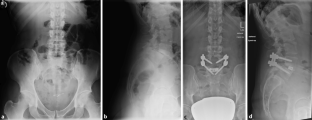

Abb. 2